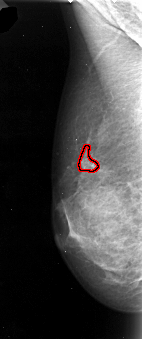

A_1096_1.LEFT_MLO

LEFT_MLO LINES 4741 PIXELS_PER_LINE 1981 BITS_PER_PIXEL 16 RESOLUTION 42 OVERLAY

FILE: A_1096_1.LEFT_MLO.OVERLAY

TOTAL_ABNORMALITIES 1

ABNORMALITY 1

LESION_TYPE CALCIFICATION TYPE PLEOMORPHIC DISTRIBUTION CLUSTERED

ASSESSMENT 4

SUBTLETY 5

PATHOLOGY MALIGNANT

TOTAL_OUTLINES 1

BOUNDARY